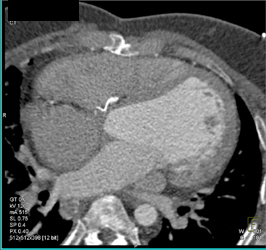

CASE NUMBER 672

Plaque on LAD